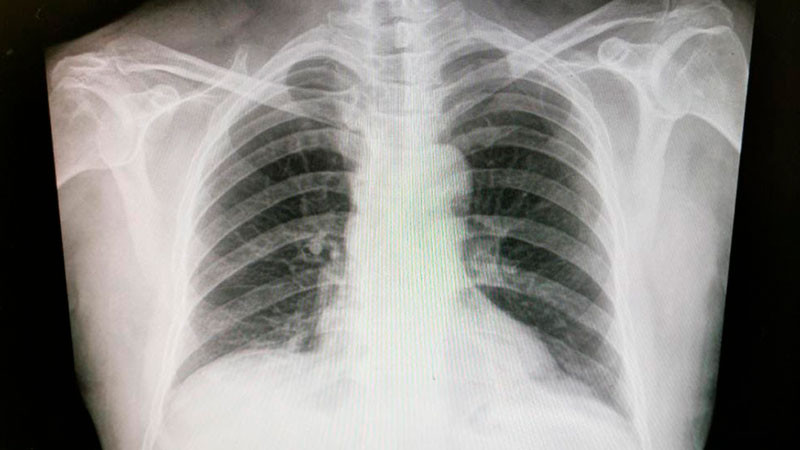

De acuerdo con el especialista, se pueden indicar estudios como radiografía de tórax, tomografías computarizadas e imágenes de resonancia magnética para identificar el interior de los pulmones; sin embargo, para detectar mutaciones genéticas e identificar el tipo de cáncer que se está desarrollando se analizan muestras del tejido pulmonar para evaluar la opción terapéutica más conveniente.